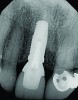

Fig 3. The root tip, after removal of the crown.

Figure 3

Without reflecting a full-thickness mucoperiosteal flap, the root tip was carefully extracted using periotomes to preserve the buccal plate and interproximal bone (Figure 3 and Figure 4). The extraction site was carefully debrided, and an osteotomy was prepared following the manufacturer’s instructions for placement of a 5/4mm D x 13mm L OSSEOTITE® Tapered Certain® PREVAIL® Implant (BIOMET 3i, www.biomet3i.com).